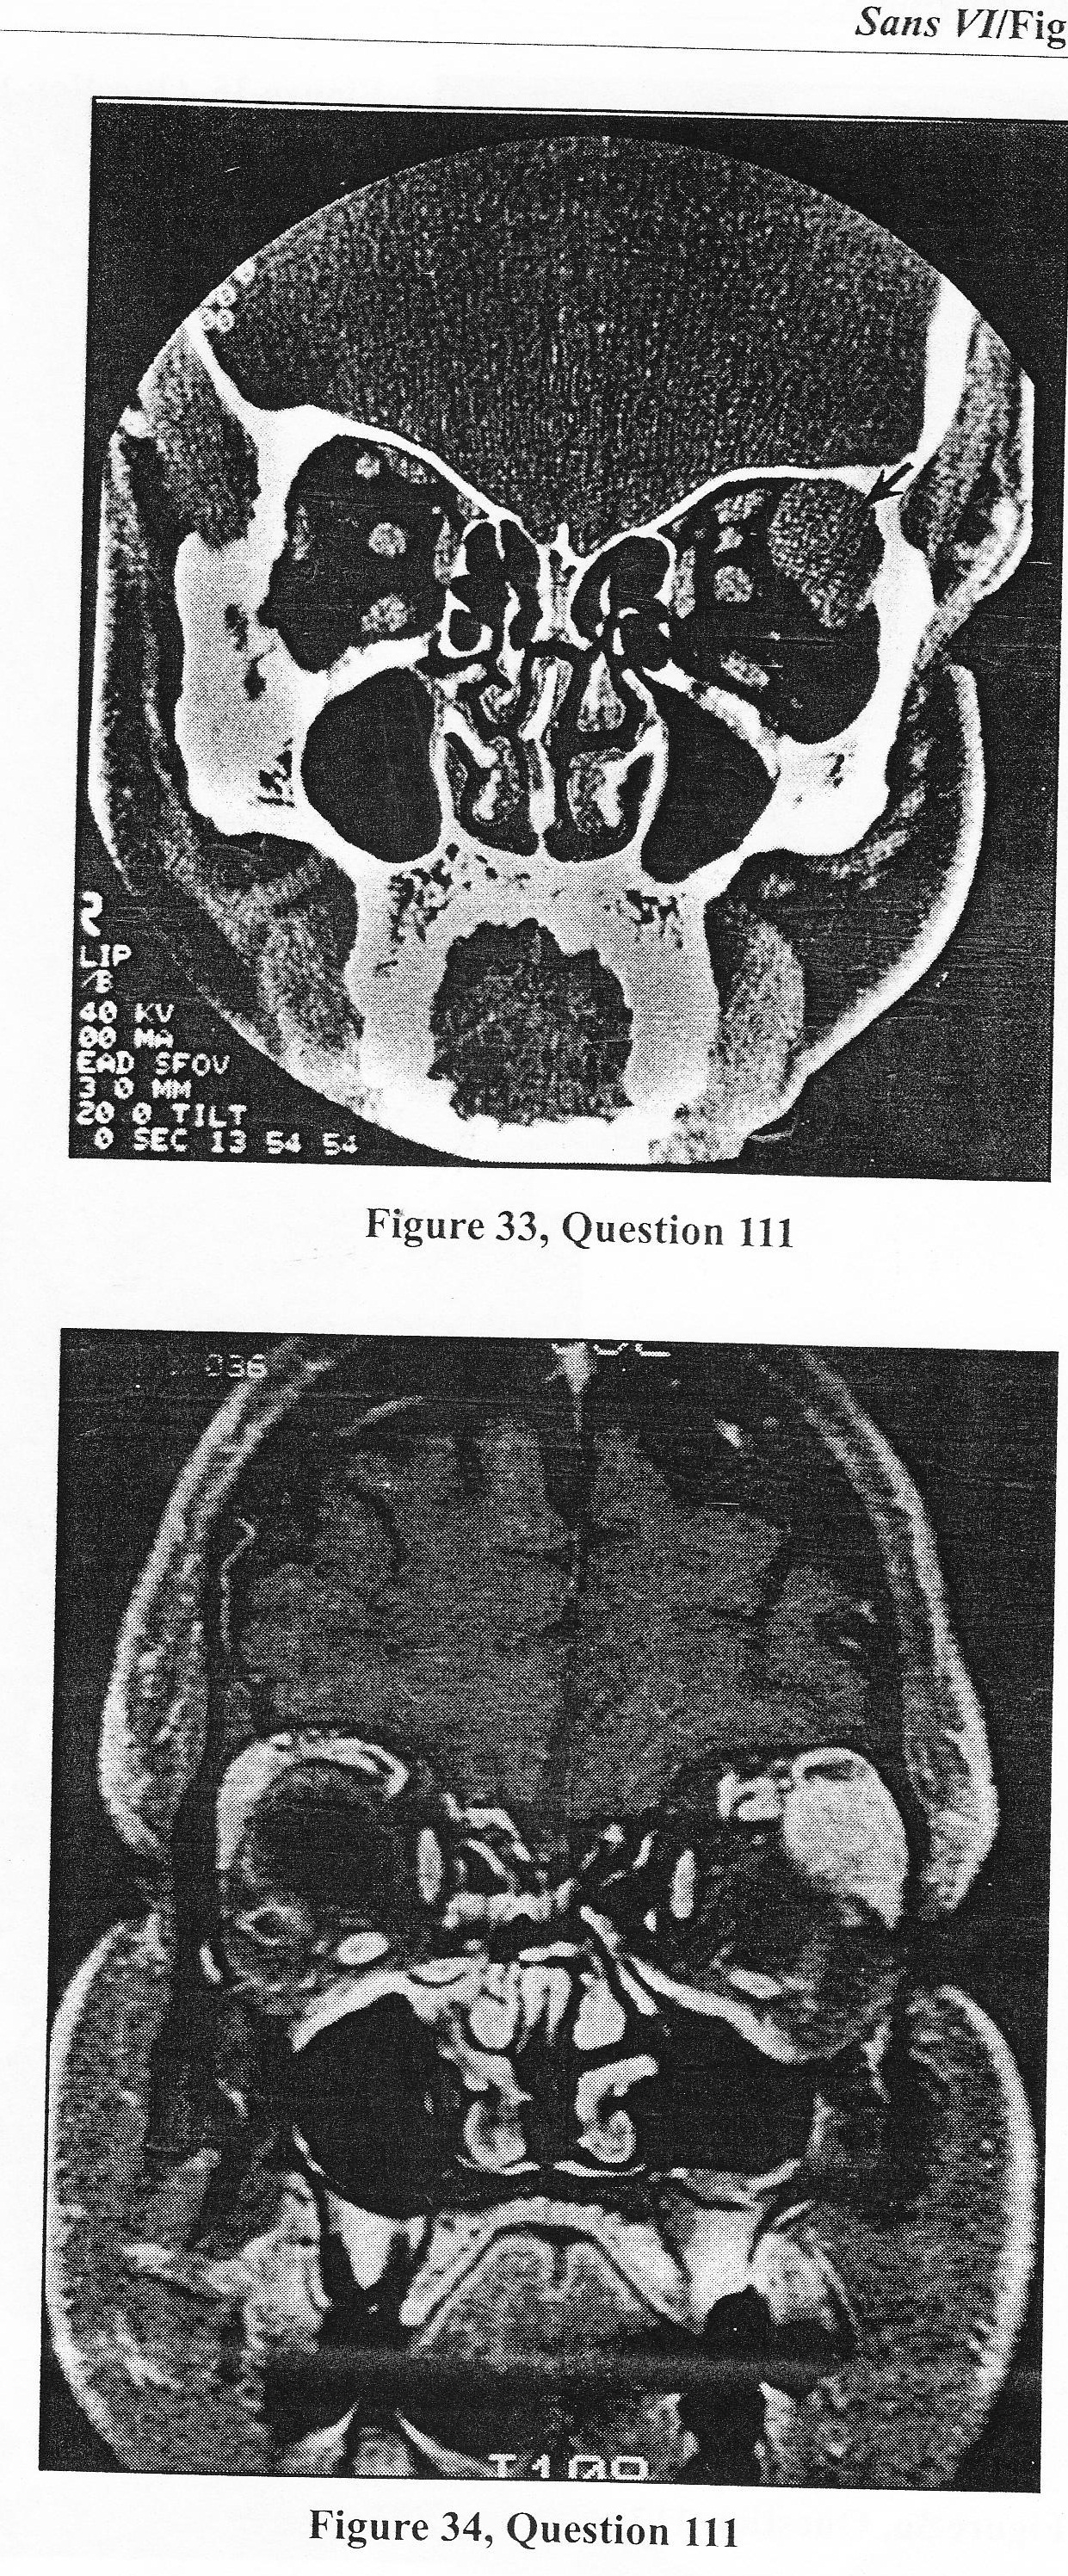

A. prescribe analgetics for hedache/cervical pain and repeat the MRI in six months to determine if the abnormality progressing

B. perform a lumbar puncture torule out a demyelinating proscess or a metastatic or infection etiology

C. propose a transoral C2-3 vertebrectomy and resection of the mass

D. propose a right retropharyngeal approach and resection of the mass